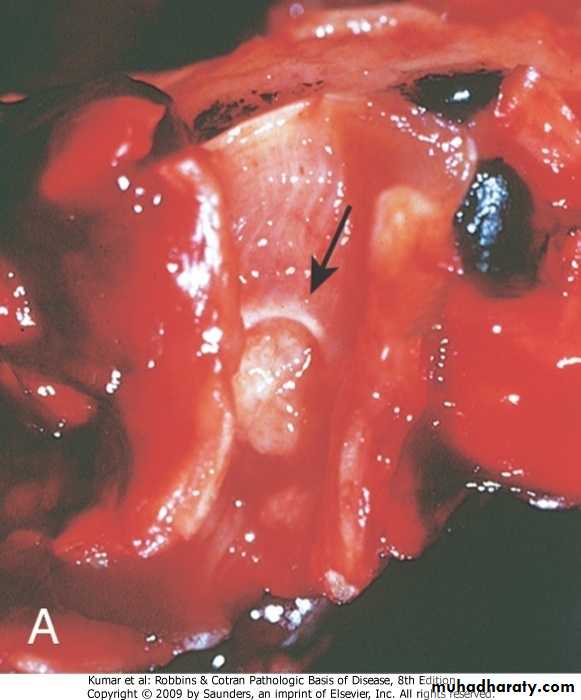

3 ,Adenocarcinoma : Arises from mucus gland in the bronchial mucosa, Consist of malignant glands with mucus secretion4.Broncho alveolar carcinoma: A form of adenocarcinoma arises from terminal bronchoalveolar region It grows on preexisting structure (alveolar wall) without its destruction

Bronchoalveolar carcinoma